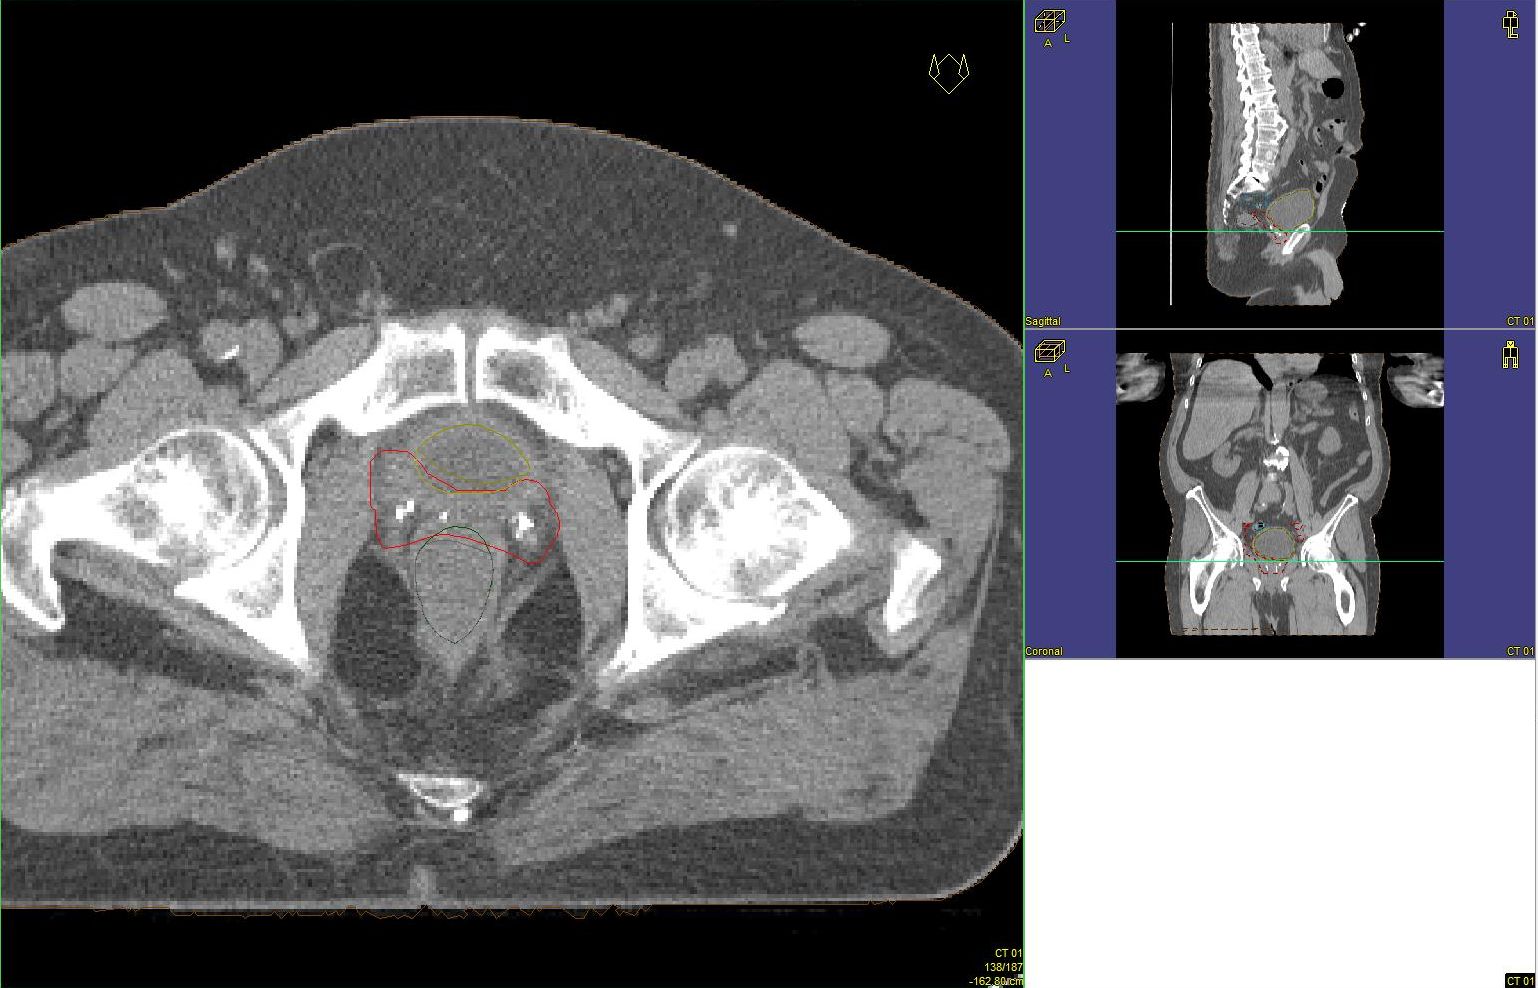

Prostata-Ca: Zielvolumen der postoperativen Radiotherapie

Beispiel: postoperative RT